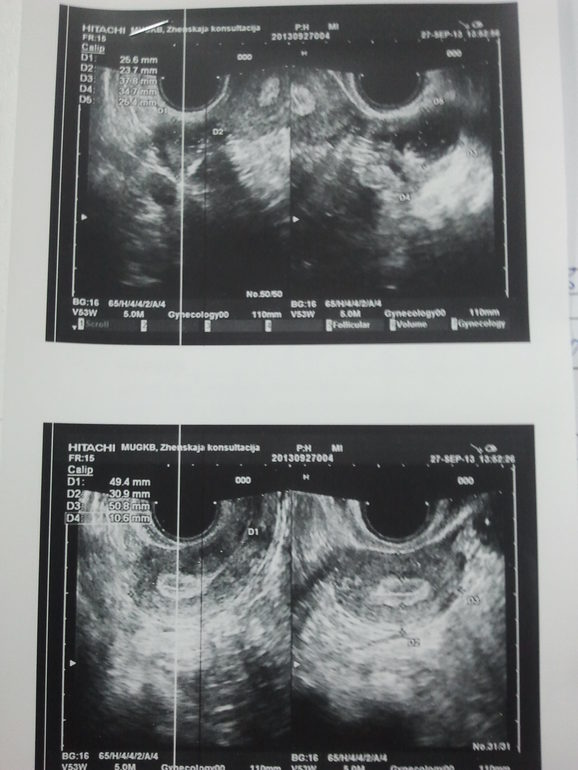

Ждем дня Х (Признаки беременности / Тесты)Добрый день!. Вот и в замешательстве прибываю((((Цикл стабильно 28дней.Мес были с 23-26 августа. на 17 д.ц пошли светло коричневые выделения.шли дней 5 по чуточку. А сейчас задержка 5тый день. Тест отрицательный. Жду хоть чего не будь. Когда шла мазьня очень тянуло низ живота и поясницу. У меня задержка так и продолжается (((Уже 7 день. Вчера тянуло живот как будто месячные пришли. А нет.......Внематочная это беда. У меня в прошлом году была. И осталась я с одной трубой.Но тогда боли были постоянные.Думаю сейчас за тестом сходить еще за одним. Тест отрицательный.Сходила на узи.Только половину не поняла.Помогите разобраться пожалуйста.Узист сказала что мазало это была овуляция у вас.

Ну начнем) Была сегодня на супер пупер чувствительном УЗИ. Врач посмотрела и сказала. Что беременности у меня нет.Плодное яйцо не обнаружено. В трубе ничего нет.В левом яичнике киста желтого тела.Была поздняя овуляция+ гормональный сбой.Вот вам и задержка.Мес до сих пор нет.Врач сказала подождать недельку и вызывать мес.Вот так закончилась моя эта история.Но врач очень грамотный и обьяснила что у меня одна труба и зачатие возможно каждый второй цикл.Так что будем стараться.А вам девочки удачи.